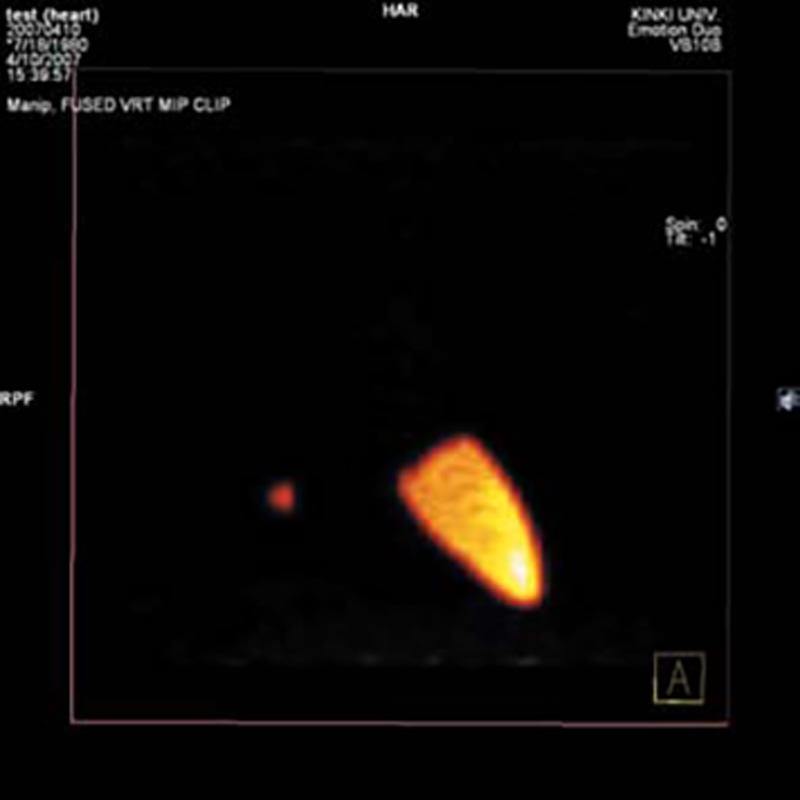

Dieses Vielzweck-Übungsmodell eignet sich für Aufnahmen mit Röntgengeräten und mit Computertomographen. Es eignet sich sowohl zum Erlernen der Aufnahmetechnik als auch für die Ausbildung der Bildinterpretation. Auch für die Gerätewartung und –einstellung eignet sich dieses Modell hervorragend. Die Strukturen des Modells sind aus Materialien mit annähernd natürlichen Röntgenabsorptionswerten gefertigt. Das Model kann geöffnet werden und künstliche Tumore können in die Lunge eingebracht werden. 15 unterschiedliche Tumore werden mitgeliefert.